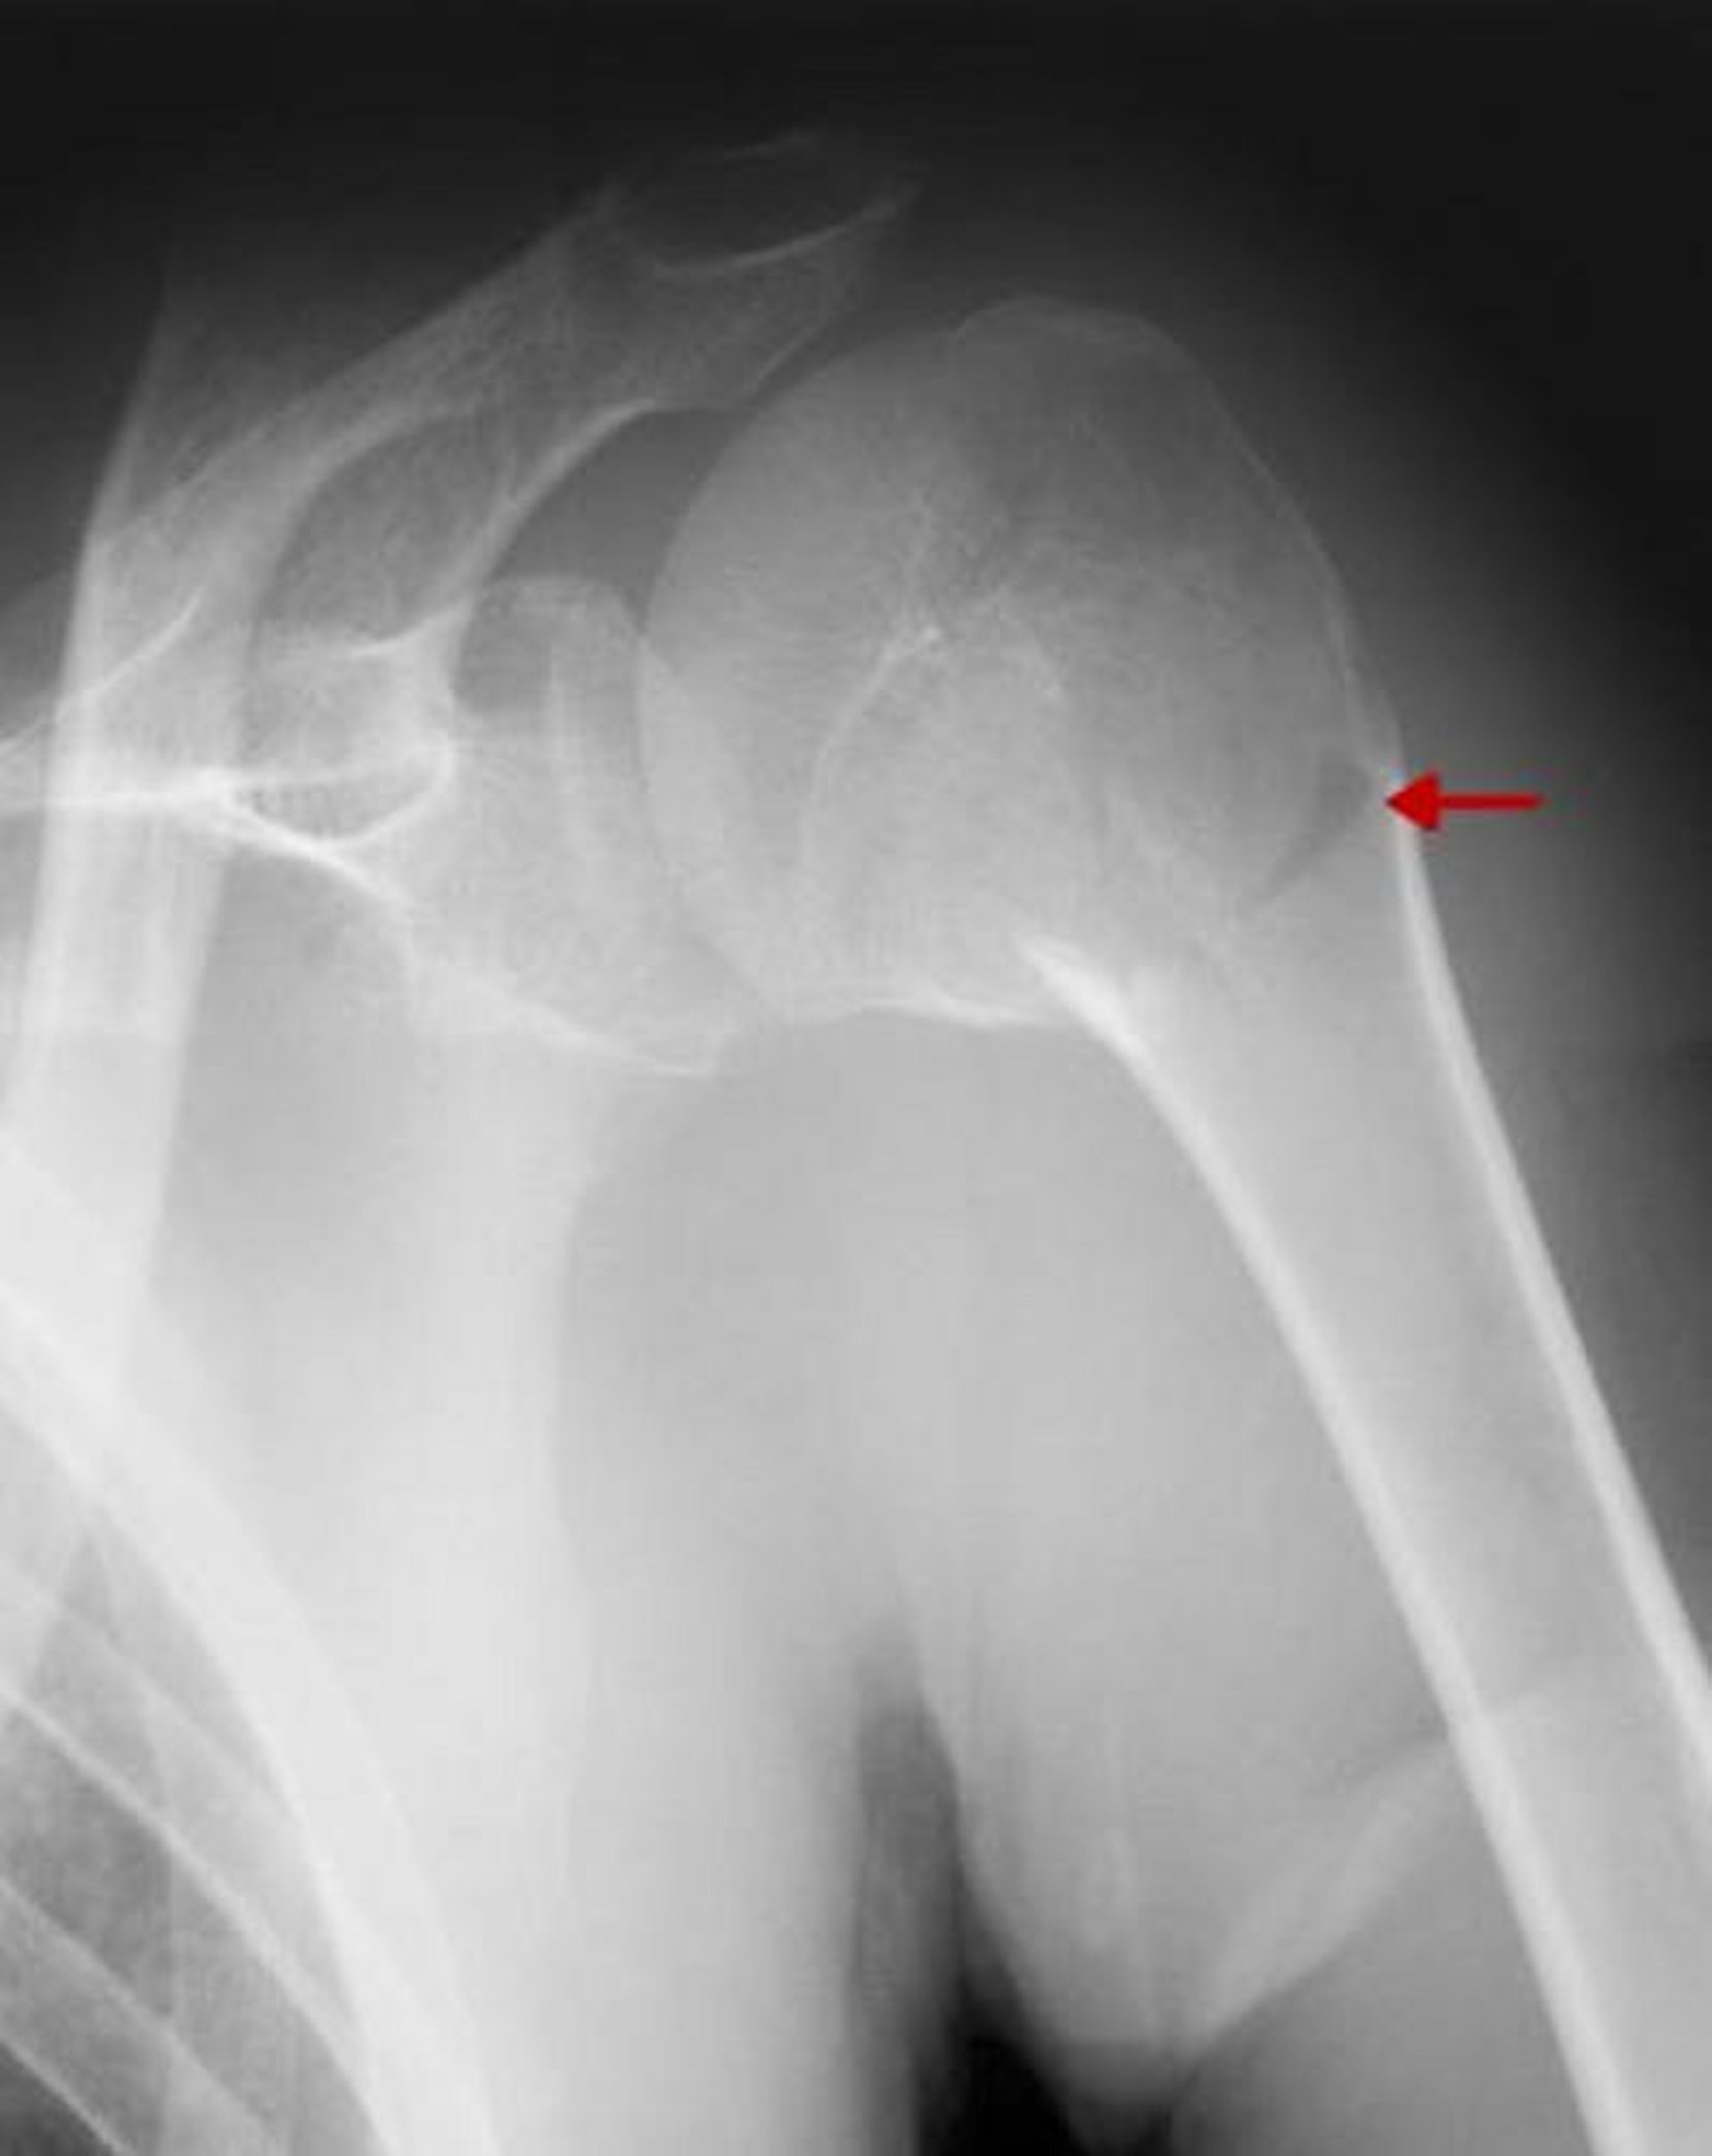

Punti di riferimento anatomici principali nell'omero prossimale

Il collo chirurgico dell'omero è fratturato.